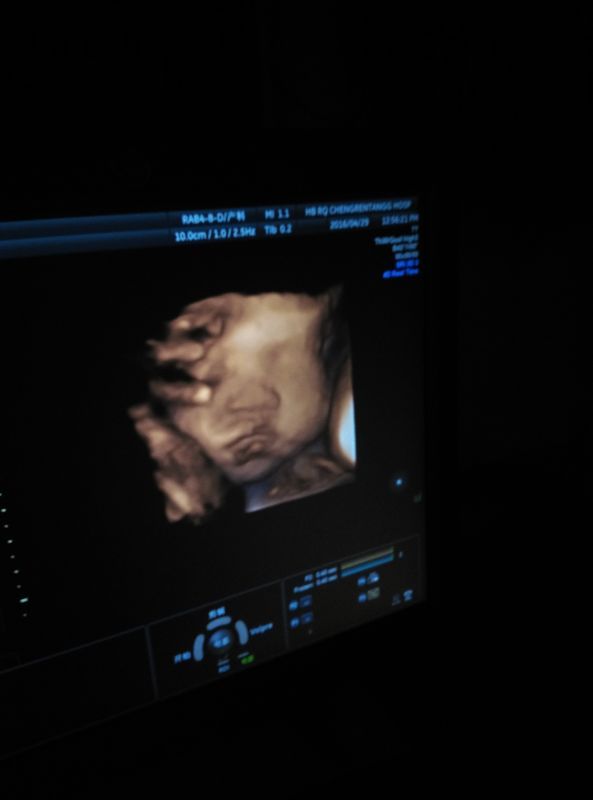

我32周时去做了一个B超,医生给孩子的正脸拍了张照片,如图 但是感觉孩子的嘴巴有点歪,嘴下还有一片 我32周时去做了一个B超,医生给孩子的正脸拍了张照片,如图。但是感觉孩子的嘴巴有点歪,嘴下还有一片阴影,像一个小球球,非常担心孩子的下巴那是长了什么东西,求助各位亲们,帮忙看看是不是畸形。 点击展开 匿名用户 2016-05-08 08:49 满意回答 没有啊 母婴用户730087652 2016-05-08 08:49 宝宝知道提示您:回答为网友贡献,仅供参考。 为您推荐: 其他回答 胎儿发育过程中,这是属于正常的,真的明显的都被你看到,b超医师没说有问题,你担心什么, 匿名用户 2016-05-08 08:51 相关问题 帮我看看B超照片,哪里是宝宝的眼睛鼻子嘴巴,在这张图上画出来好吗?谢谢了!企鹅397582475 急急,孩子有时嘴巴抖,脚有时抖一下,怎么回事,医生说缺钙,你们孩子有这种情况没 今天去照B超,医生说看不到宝宝嘴巴 心里发毛,很害怕